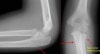

X-ray : 요골경 골절(Radial neck fracture, 요골두 골절과 마찬가지로 팔을 쭉 펴고 낙상시 발생)

보통 AP, lateral, both oblique 즉 4장의 사진을 모두 찍어야 미세한 골절을 찾아내기 수월합니다.

필요시 요골두-소두 촬영을 실시합니다.

손을 신전 상태에서 손을 짚고 넘어지면서 직접적인 축성 부하나 외반력에 의해 요골두와 소두와 충돌하여 골절이 발생합니다.